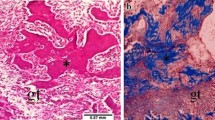

Figure 1 shows the optical microscopic views of the tooth extraction sockets on every experimental day in all the groups. Three days after extraction, the sockets in group 1 were filled mainly with red blood cells (RBCs), inflammatory cells, and fibroblasts from the remnants of the periodontal ligaments (PDL). In group 2, there was less infiltration of inflammatory cells than observed in the non-irradiated group, and newly formed collagen fibers, osteoclasts, and more fibroblasts were observed. In group 3, many inflammatory cells and RBCs were densely infiltrated near the top of the socket. Fewer fibroblasts and collagen fibers than in the other groups were observed. In group 4, there were fewer inflammatory cells and RBCs and more infiltrated fibroblasts than in group 3.

Optical microscopic views of the tooth extraction sockets (H&E stain). The differences in healing were dependent on whether the sockets had received laser irradiation. LLLT promoted not only early healing, such as the reduction of inflammatory cells and the proliferation of fibroblasts but also the emergence of osteoblasts and bone formation under both normal and diabetic conditions. At day 14, the original magnification 40× was used to observe the entire socket. The amount of new bone and osteoid tissue was higher in group 2 than in group 1 and higher in group 4 than in group 3

Five days after extraction, the RBCs had almost disappeared in all groups and newly formed vessels, connective tissue, and fibroblasts were observed. In group 2, the collagen fibers were denser near the residual PDL, and osteoid tissue and lining osteoblasts were observed from the base area of the socket. In groups 1 and 4, concentrated fibroblasts, thick collagen fibers around them, osteoblasts, and some osteoid-like matrix were observed near the old alveolar bone.

At 7 days, new bone, osteoid and lining osteoblasts around them were observed in all groups, but there were some differences in the amount of new bone and osteoid tissue. There were more cells and connective tissue than at 5 days.

At 14 days after extraction, new bone, lining osteoblasts, osteocytes, osteoid, thick collagen fibers, and fibroblasts were observed in all groups. In group 2, the sockets were almost completely filled with new bone and there was more new bone than in group 1. In group 3, bone formation was poorer than any of the other groups. Only one-third of the sockets were filled with new bone; the remainder were filled with connective tissue. In group 4, new bone filled approximately one-half of the socket. Bone formation in group 4 was more prominent than in group 3.

The results of this study also showed a biostimulatory effect of LLLT on the alveolar bone of both normal and diabetic rats. In group 2, osteoblasts and osteoid tissue were observed at day 5, which was earlier than in the control group, and new bone reached the top of the extraction socket at day 14. In group 3, healing was much slower than in group 1. At day 3, considerable infiltration of inflammatory cells and blood clots in the superficial part of the sockets were observed in group 3. The amount of new bone and osteoid tissue in group 3 was the lowest of all the groups at days 7 and 14. In group 4, much less infiltration of inflammatory cells and blood clots were observed than in group 3 at day 3, and more new bone formed at days 7 and 14 than in group 3, even though only half of the extraction socket was filled with new bone at day 14. The differences in healing were dependent on whether the sockets had received laser irradiation. LLLT promoted not only early healing, such as the reduction of inflammatory cells and the proliferation of fibroblasts but also the emergence of osteoblasts and bone formation under both normal and diabetic conditions.